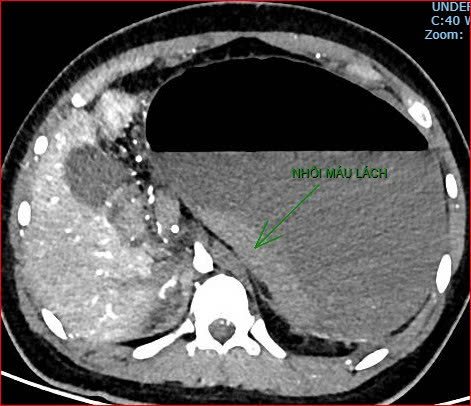

Khoảng 21 giờ 40, kết quả chụp CT cho thấy bệnh nhân rơi vào tình trạng cực kỳ nặng và hiếm gặp, bao gồm: xoắn dạ dày, nhồi máu thận trái, nhồi máu lách, viêm đầu tụy, viêm hỗng tràng, kèm dịch ổ bụng và tràn dịch màng phổi, trên nền bệnh nhân mắc hội chứng Down và tim bẩm sinh.

Hình ảnh chụp CT ổ bụng cho thấy dạ dày giãn lớn, xoắn bất thường; kèm tổn thương nhồi máu lách và viêm tụy trên nền ca bệnh hiếm, diễn biến đặc biệt nặng - Ảnh Bệnh viện cung cấp |